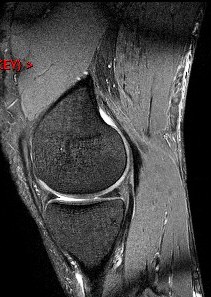

Figure 4 for case Semitendinosus tendon tear, retracted( RID2717 )

Figure 4